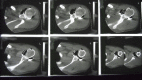

Methods: Forty-seven patients were treated with a primary modified open Bankart repair for recurrent anterior shoulder instability between 1989 and 1994. Double-contrast computed tomography scanning was used to exclude patients with a substantial osseous glenoid defect. Forty patients (85.1%) were available for subjective and objective follow-up at a minimum of twenty years (maximum, twenty-five years). Twenty-six patients (65%) underwent clinical examination as well as bilateral shoulder radiography, and fourteen (35%) completed a self-assessment questionnaire and were interviewed by telephone.